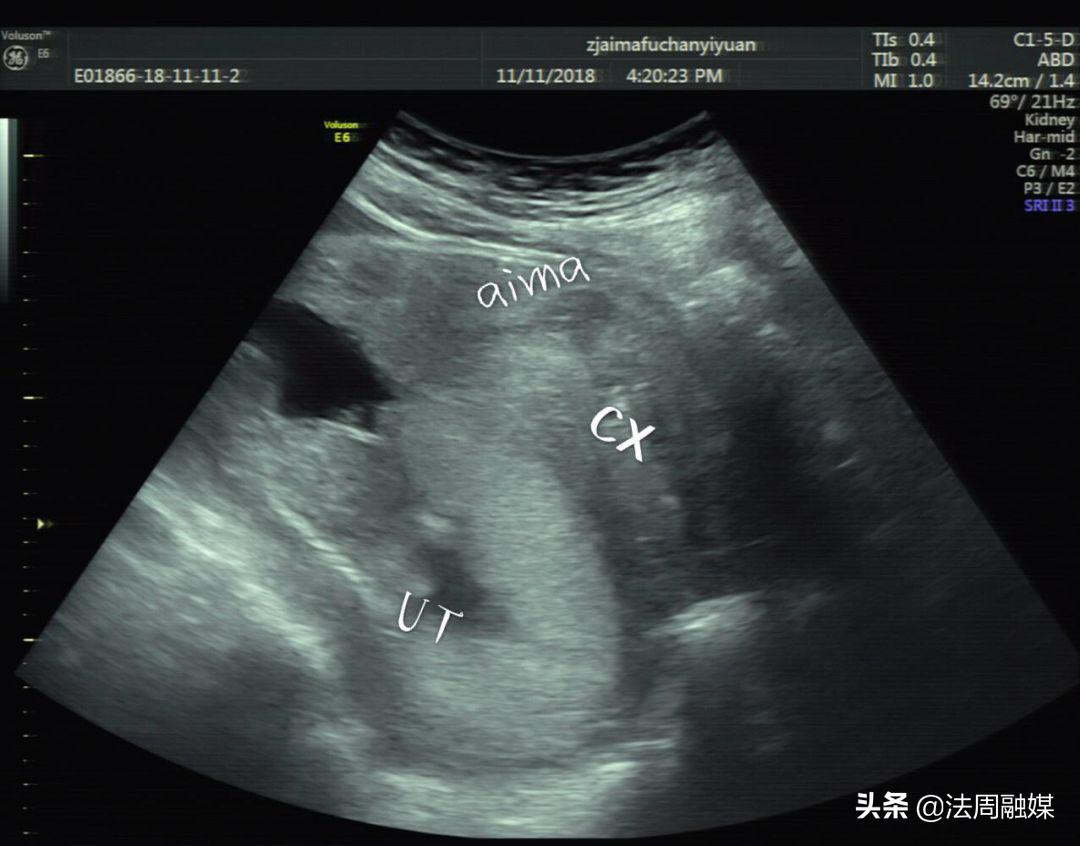

膀胱明显充盈表现细长,后方见妊娠子宫回声

子宫明显后倾后屈,宫颈细长